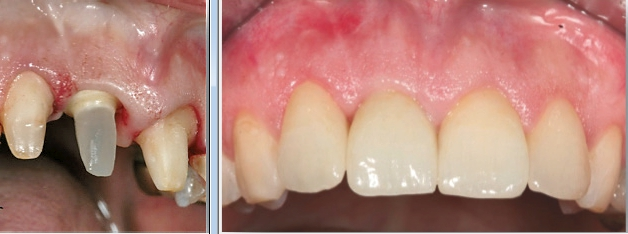

98 % aller Patientenfälle können wir im MIMI-Verfahren durchführen, welches z. B. für eine Einzelzahnversorgung lediglich zwei Patientensitzungen benötigt, im Gegensatz zu fünf oder sechs Sitzungen im konventionellen Verfahren:

- Erste Sitzung: Implantation mit eventuell simultan durchgeführter, horizontaler Augmentation von schmalen Kieferkämmen (MIMI II) und interner, direkter Sinuslift (IDS, MIMI V) – gänzlich ohne Mukoperiostlappenbildung, Abformung und Bissnahme.

- Zweite Sitzung: Eingliedern der Krone(n) (Abb. 1 bis 8).